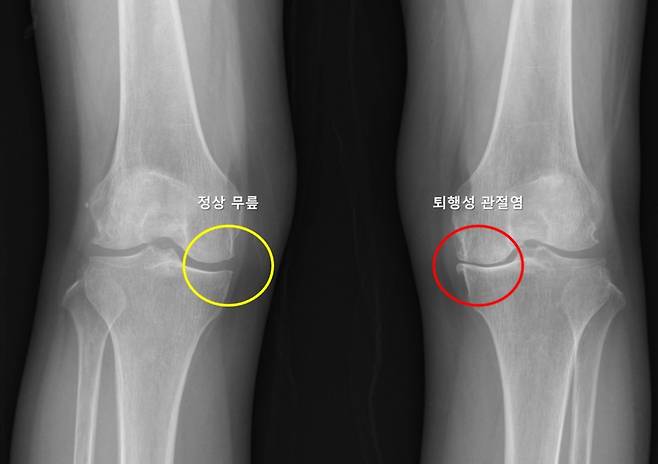

한쪽 무릎에 퇴행성 관절염이 생긴 환자는 다른쪽 무릎에도 똑같은 병이 생기지 않을지 불안에 떨어야 했다. 많은 환자가 한쪽 무릎에 관절염이 생긴 뒤 수년 내 반대쪽 무릎에서도 통증, 구조적 변화가 나타나는 경험을 한다. 하지만 이러한 양측성 진행이 모든 환자에게서 똑같이 나타나지 않아, 이를 예측하려는 연구는 부족했다. 그런데 서울대병원 연구팀이 이런 예측을 가능하게 하는 머신러닝 기반 모델을 개발하는 데 성공했다.

분석 결과, 예측에 가장 큰 영향을 미친 요인은 성별이었으며, 반대쪽 무릎의 외측 관절 간격 감소, 반월판 절제술 병력, BMI 등이 그 뒤를 이었다. 특히, 반대쪽 무릎의 외측 관절 간격 감소는 통계적으로 가장 높은 위험 비율(odds ratio 4.475)을 보여, 반대쪽 무릎 퇴행성 관절염 발생 위험을 약 4.5배 증가시키는 주요 요인으로 확인됐다.

또 기존 관절염이 있는 무릎의 관절염 정도(KLG)와 통증 및 기능 지표(WOMAC 점수)가 반대쪽 무릎 퇴행성 관절염 발생과 유의미한 연관성을 보인 것은 이번 연구에서 처음 확인된 중요한 결과다. 성별이나 BMI 등 기존에 알려진 일반적 위험 요인 외에도, 반대쪽 무릎 자체의 구조적 특성이 관절염 발생 예측에 중요한 역할을 했으며, 이전까지 잘 알려지지 않았던 외측 관절 간격 감소가 핵심 예측 요인으로 확인된 점 역시 이번 연구의 의미 있는 발견으로 꼽힌다.